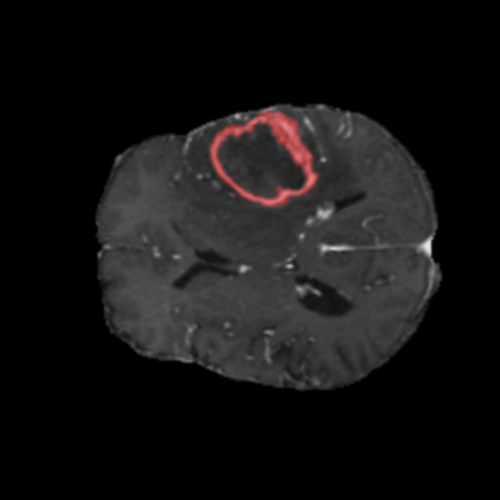

Ejemplos LGG - Atención Difusa en Edema Peritumoral

LGG Grad-CAM++ 1 LGG Grad-CAM++ 2 LGG Grad-CAM++ 3 LGG Grad-CAM++ 4 LGG Grad-CAM++ 5 LGG Grad-CAM++ 6

Para casos LGG, la atención del modelo es más difusa y se concentra principalmente en la región de Edema Peritumoral (verde), consistente con la naturaleza más infiltrativa y menos agresiva de estos tumores.